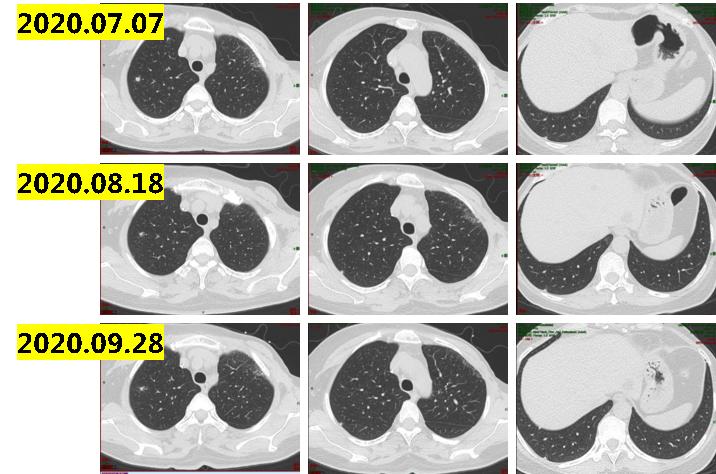

2020.05~2020.09行6周期白蛋白紫杉醇,期间疗效评价为SD(图1-2)。2020年8月国产氟维司群上市,为减轻患者的负担,国产氟维司群上市之后给予中国患者相应的援助项目。在慈善赠药的帮助下,2020.09~2021.06患者接受氟维司群维持治疗9个月,于当地定期复查疗效评价为SD。

2021.6.10复查肺部ct示:双肺散在实性结节,最大10×8mm,部分病灶较前稍增大;纵隔及肺门淋巴结增大,最大直径13mm(图1-3),考虑病情进展。

图1-2

图1-3